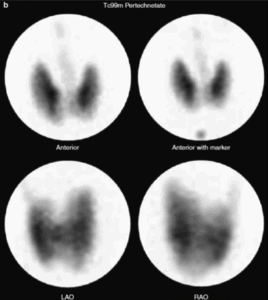

2. Scintigrafia tiroidea

La scintigrafia con Tc-99m o I-123 consente di visualizzare la distribuzione del tessuto tiroideo funzionante e identificare eventuali aree iperfunzionanti (noduli autonomi) o assenza di captazione.

Questa informazione è essenziale per distinguere tra Morbo di Basedow (captazione diffusa) e gozzo multinodulare tossico (captazione disomogenea), oltre che per escludere sospetti di neoplasia, in cui la captazione può essere assente.